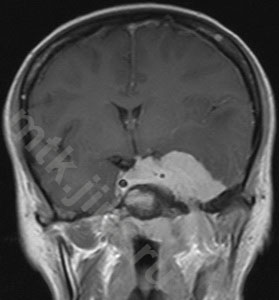

Пример лечения

План конформной протонной лучевой терапии большой (132.5 см3) менингиомы средней черепной ямки (слева), МРТ с контрастом до лечения в середине и МРТ через 12 мес после лечения (справа) – заметное уменьшение опухоли.